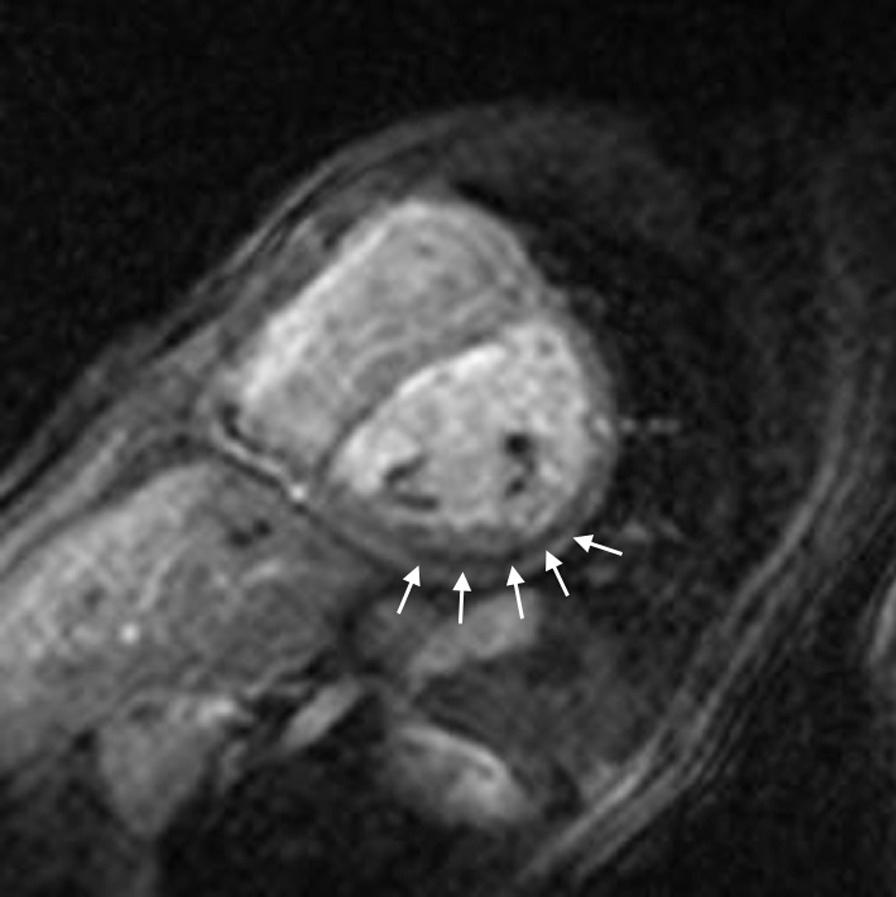

Cardiovascular magnetic resonance (CMR) has been utilized in the management and care of pediatric patients for nearly 40 years. It has evolved to become an invaluable tool in the assessment of the littlest of hearts for diagnosis, pre-interventional management and follow-up care. Although mentioned in a number of consensus and guidelines documents, an up-to-date, large, stand-alone guidance work for the use of CMR in pediatric congenital 36 and acquired 35 heart disease endorsed by numerous Societies involved in the care of these children is lacking. This guidelines document outlines the use of CMR in this patient population for a significant number of heart lesions in this age group and although admittedly, is not an exhaustive treatment, it does deal with an expansive list of many common clinical issues encountered in daily practice.

心血管磁共振(CMR)在儿科患者的管理和护理中已经应用了近 40 年。它已经发展成为评估最小的心脏的宝贵工具,用于诊断、介入前管理和随访。尽管在许多共识和指南文件中提到,但在儿科先天性心脏病和后天性心脏病领域,目前还缺乏一份由众多参与儿童护理的学会共同认可的、最新的、独立的、针对 CMR 使用的大型指南。本指南文件概述了 CMR 在该年龄段的许多心脏病变中的应用,尽管不能说是详尽的治疗方法,但它确实涉及了在日常实践中经常遇到的许多常见临床问题的广泛列表。